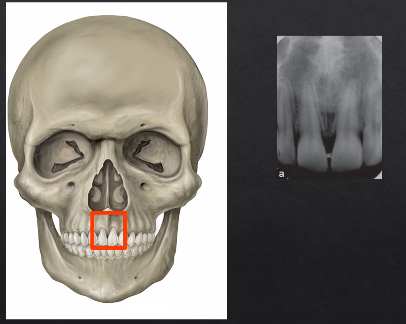

planar projections

posterior/anterior mandible, lateral cephalogram

called posterior/anterior because the Xrays are coming from the posterior to the anterior, detector is touching the patient’s face and the Xrays are coming from behind

Xrays hit the detector at 90 degrees

image would form something like this - this is a PA → posterior anterior mandible is